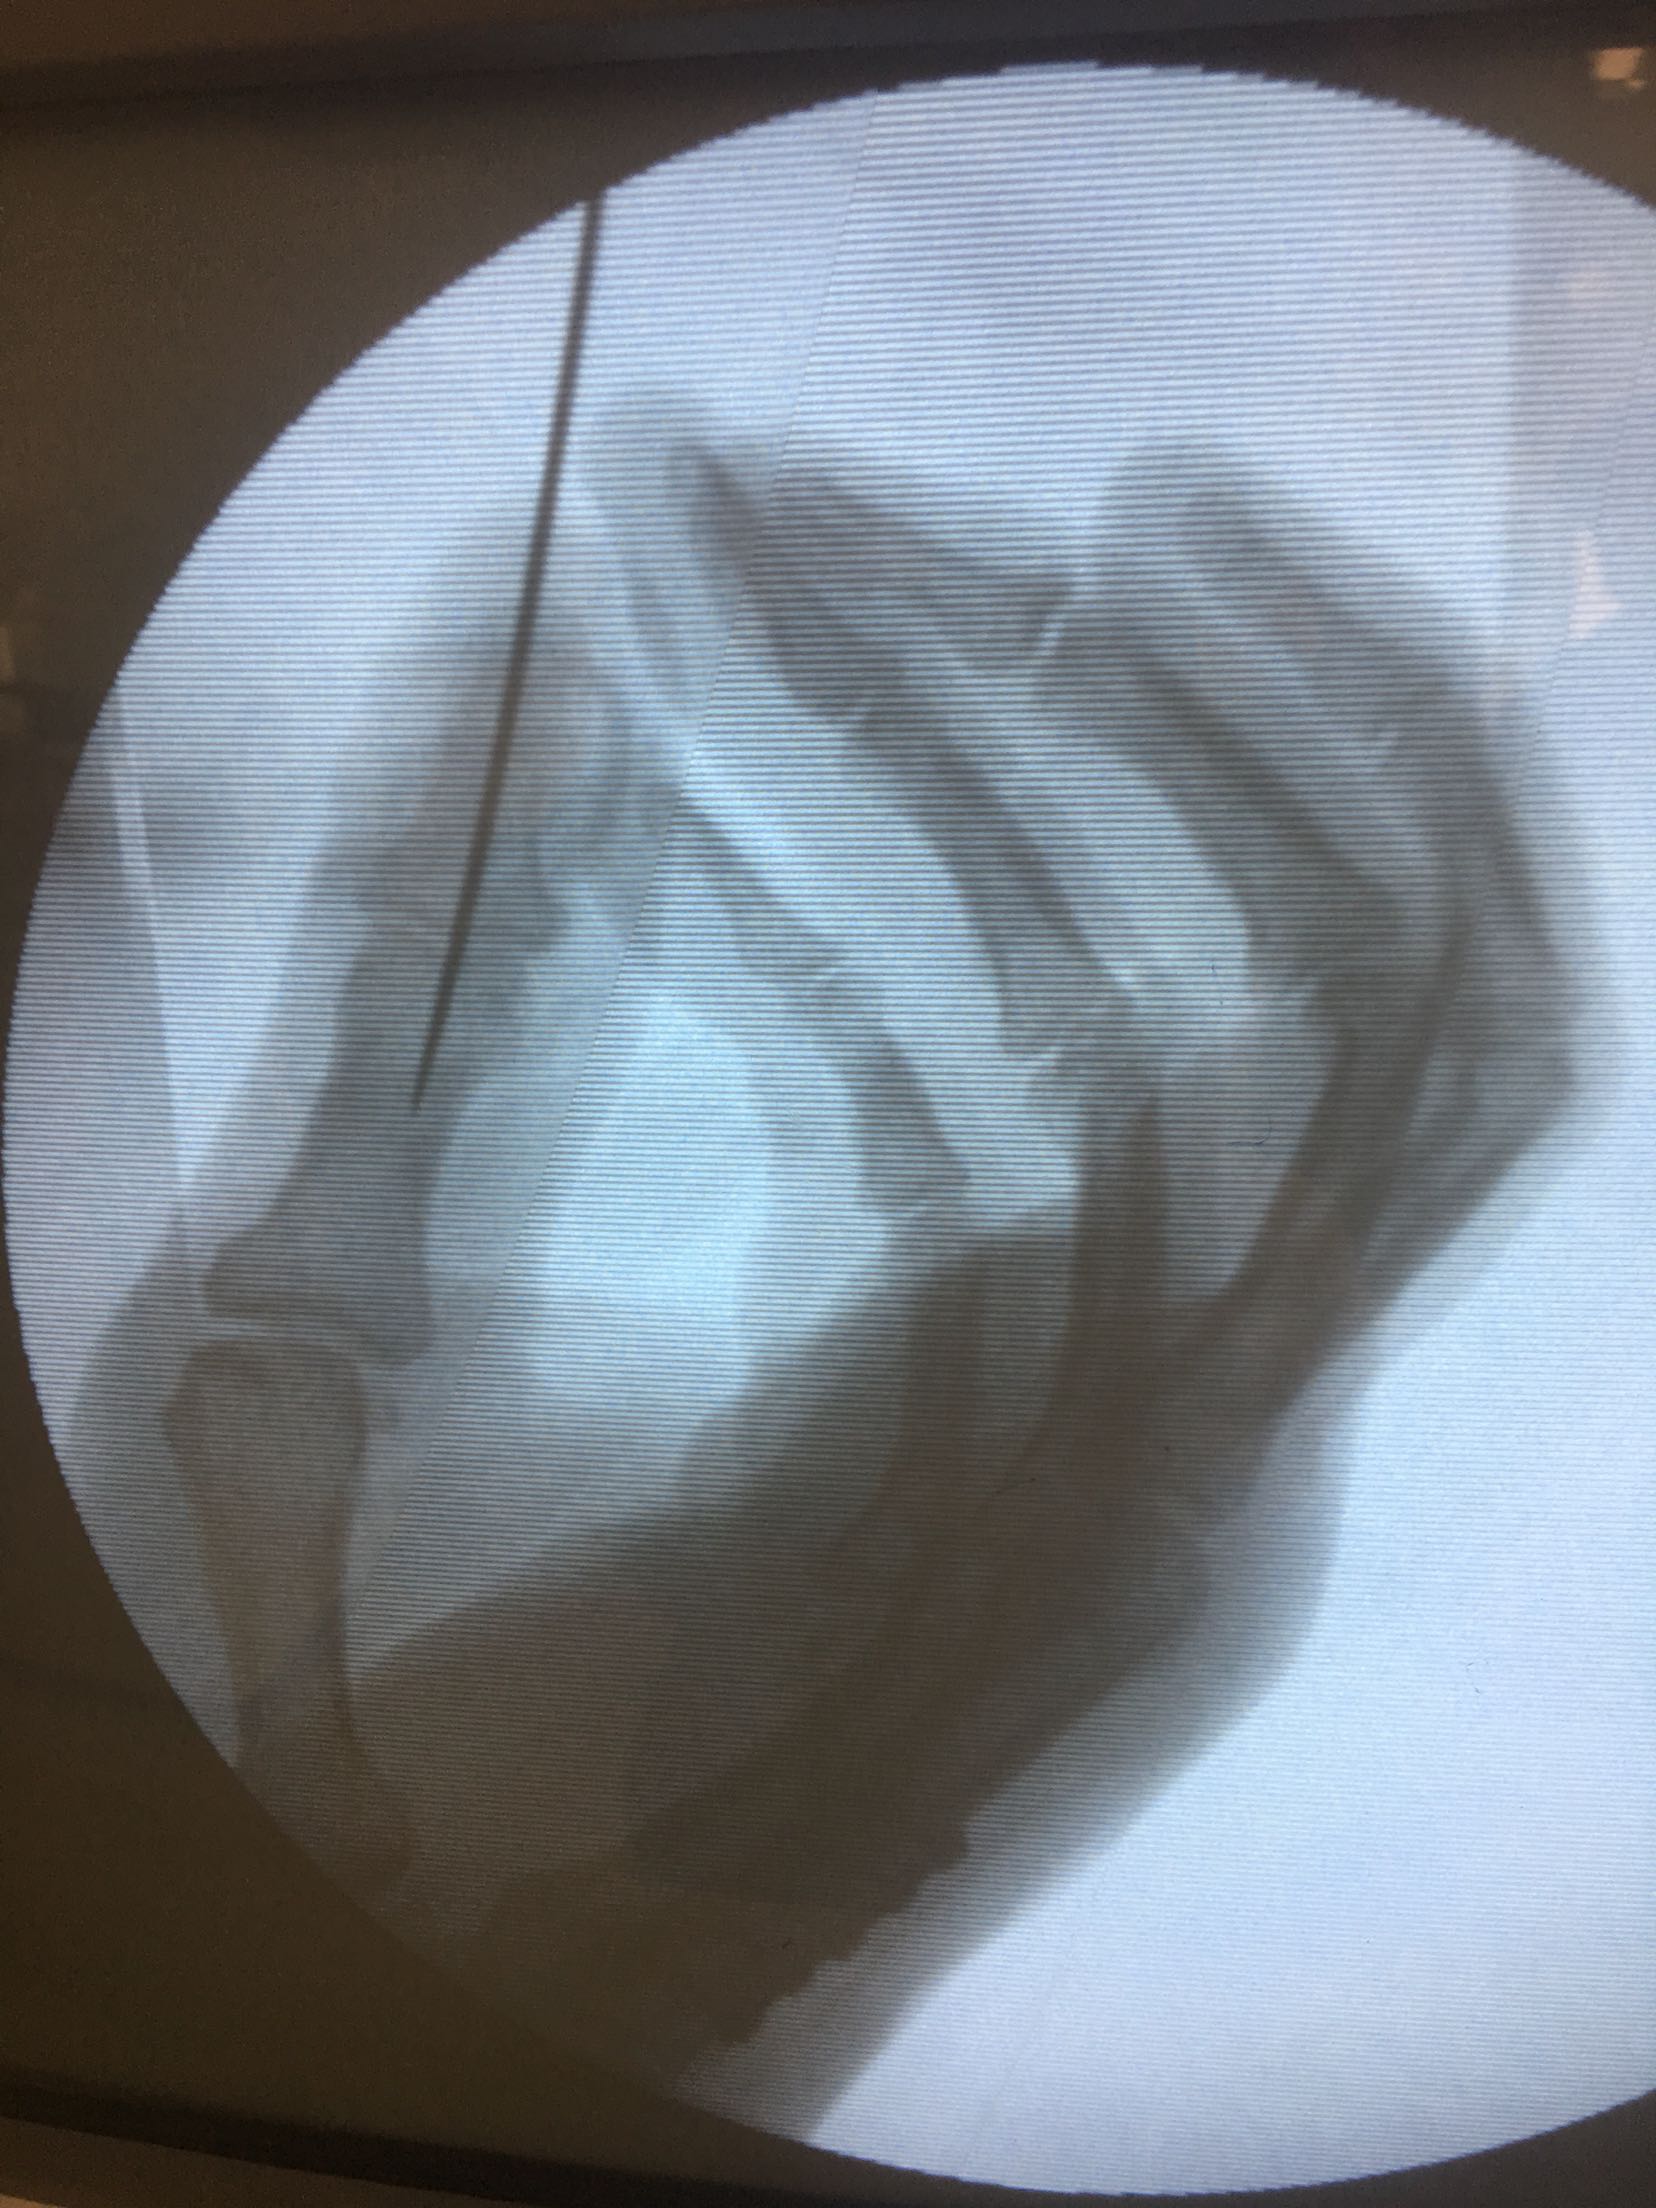

积极术前准备,在臂丛麻醉下行锤状指伸指功能重建术,掌骨骨折切复内固定术,术后抗炎,消肿对症处理。<img src=https://pub-voice-video.medlinker.com/9129333F-3928-47F0-B39A-978756FECFAD><img src=https://pub-voice-video.medlinker.com/945D4FD6-D0B7-41EF-ABB0-C2940D6C2E54><img src=https://pub-voice-video.medlinker.com/2F847276-23A8-4CAF-BF99-1828976F7BAD><img src=https://pub-voice-video.medlinker.com/2996EABA-9281-4CC0-8612-66A515AC6472><img src=https://pub-voice-video.medlinker.com/D3EFB6D4-D26D-4778-B65E-2D52DD5235E7><img src=https://pub-voice-video.medlinker.com/9197F543-FC48-48BB-BA43-DDBEEE8749C0><img src=https://pub-voice-video.medlinker.com/109E9BC2-A473-4E71-B880-027E2D1DF300>